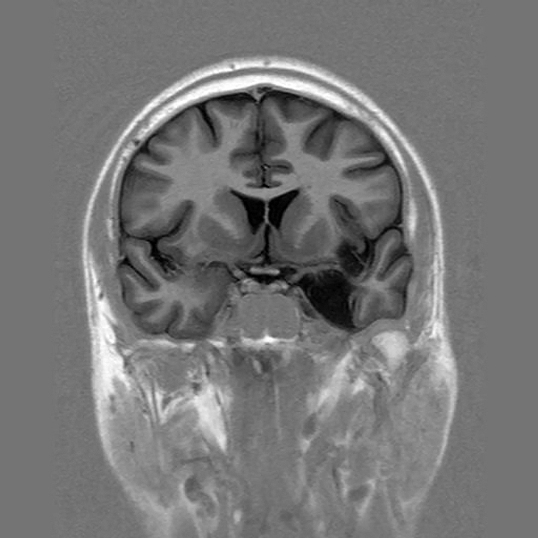

The functionality of memory resides fundamentally in the medial temporal lobe, being the hippocampus a crucial zone for the phase of memorization, and the neocortex for storage, which is why the deterioration of this encephalic fraction originates the amnestic, different- degree syndrome depending on the part and the extension of the injury. With alteration of the declarative memory when the left-hand hippocampus is affected, being the most evident deterioration in the anterograde memory (what goes succeeding after the brain damage) although, the retrograde memory (what is right now registered) can also fail, now then, memory not declarative he keeps in good condition so that the person holds qualifications or simple habits as driving a bicycle or more complexes like managing programs of information technology.

The importance of the hippocampus in the declarative memory, attested for Ramon Y Cajal in 1910, became patent with HM's case in 1953, epileptic refractory patient to the treatment, that he was a resection submittedly that the hippocampus losing the capacity of storing new information included but that, however, maintained their habits and skillful actions motive, what the fact that the left-hand hippocampus's damage creates harsh problems for the storage of new reports confirms, so much of names as of numbers. The cerebrovascular traumatisms are at present the causes of the great majority of amnestic processes, most of all in young people, to minor level tumors and encephalitis, between other causes like the Alzheimer's disease that often he debuts with the loss by heart for atrophy, generally bilateral, of the hippocampus.

We counted on various diagnostic specific proofs, like the tomography for emission of positrons, the magnetic functional resonance or the magnetoencephalography, existent in few sanitary centers, that they can determine the mnestic deterioration that does not manage to evaluate with intervening efficacy in the neuropsychological proofs.